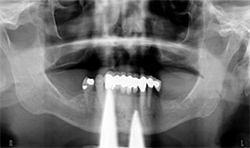

A 71-year-old male presented with a full maxillary denture and retained lower left canine and lower right first premolar (Fig. 3). He desired a semi-permanent solution to improve fit, function of upper and replace all missing teeth on the lower. An initial panoramic radiograph was taken for surgical and restorative planning purposes. The patient and doctor discussed options and it was decided a new maxillary full denture and a fixed hybrid prosthesis on the lower arch would be acceptable treatment options.

Fig.3